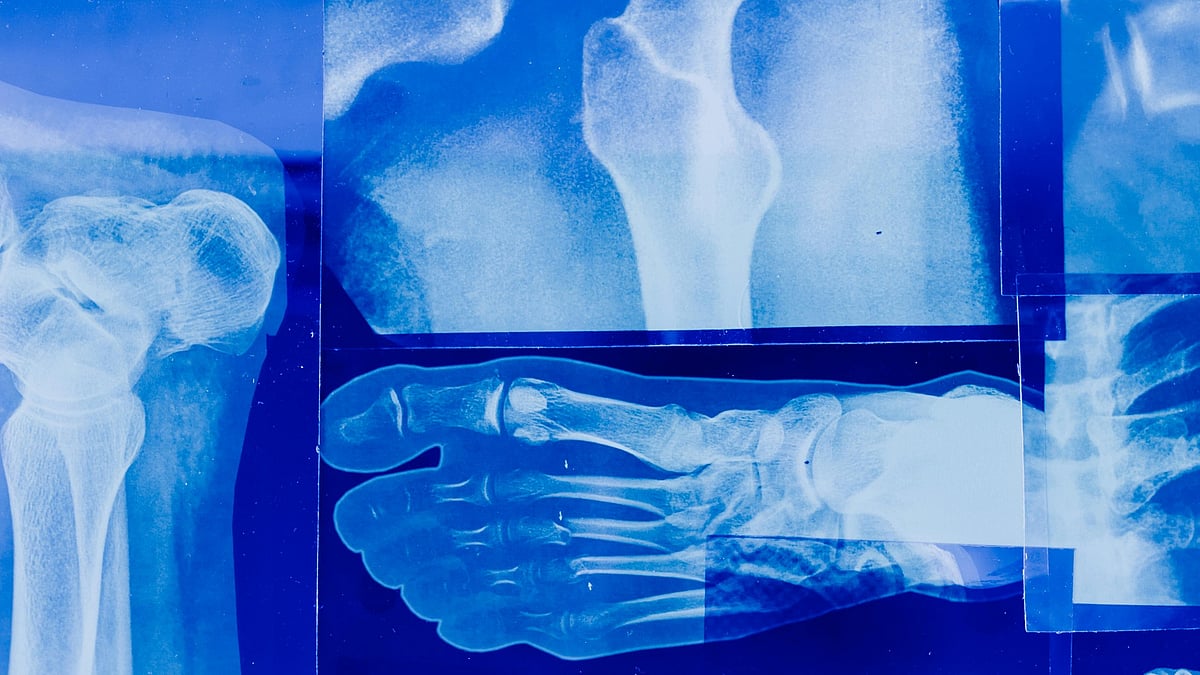

বিভিন্ন ধরনের দুর্ঘটনায় হাত-পায়ের হাড় ভেঙে যায় অনেকের। ভাঙা হাড় চাইলেই দ্রুত জোড়া দেওয়া যায় না, দীর্ঘ মেয়াদে চিকিৎসার প্রয়োজন হয়। এবার ভাঙা হাড় দ্রুত জোড়া দেওয়ার জন্য বিশেষ ধরনের আঠা তৈরি করেছেন চীনের একদল গবেষক। গবেষকদের দাবি, ঝিনুকের প্রাকৃতিক এক কৌশল কাজে লাগিয়ে তৈরি বিশেষ ধরনের এই আঠার মাধ্যমে মাত্র তিন মিনিটের মধ্যে ভাঙা হাড় জোড়া লাগানো যাবে। নতুন এই আবিষ্কার অর্থোপেডিক চিকিৎসায় এক নতুন দিগন্ত খুলে দিতে পারে বলে ধারণা করা হচ্ছে।

গবেষকদের তথ্যমতে, ‘বোন ০২’ নামের এই আঠা ব্যবহার করে ভাঙা বা টুকরা হয়ে যাওয়া হাড়কে মাত্র দুই থেকে তিন মিনিটের মধ্যে জোড়া লাগানো যাচ্ছে। এ বিষয়ে গবেষক দলের প্রধান সার রান রান শ হাসপাতালের অর্থোপেডিক সার্জন লিন শিয়ানফেং বলেন, পানির নিচে কীভাবে ঝিনুক কোনো কাঠামোর সঙ্গে শক্তভাবে লেগে থাকে, তা পর্যবেক্ষণ করে আমরা এই আঠার ধারণা পাই। এই আঠা রক্তের উপস্থিতিতেও নিখুঁতভাবে কাজ করতে পারে।

গবেষকেরা দাবি করছেন, হাড়ের জন্য তৈরি বিশেষ আঠাটি ঐতিহ্যবাহী ধাতব ইমপ্লান্ট যেমন প্লেট ও স্ক্রুকে প্রতিস্থাপন করতে পারে। আঠার সবচেয়ে বড় সুবিধা হলো, হাড় জোড়া লাগার পর এটি প্রাকৃতিকভাবেই শরীরের সঙ্গে মিশে যায়। স্ক্রু বা অন্যান্য ইমপ্লান্ট সরালে অনেক সময় দ্বিতীয়বার অস্ত্রোপচারের প্রয়োজন পড়ে। এ ক্ষেত্রে তার প্রয়োজন হবে না। এই আঠা সংক্রমণের ঝুঁকিও কমাবে।

এখন পর্যন্ত বোন ০২ আঠা ১৫০ জনের বেশি রোগীর ওপর সফলভাবে পরীক্ষা করা হয়েছে। পরীক্ষায় দেখা গেছে, আঠা দিয়ে জোড়া লাগানো হাড় ৪০০ পাউন্ডের বেশি চাপ সহ্য করতে পারে। ফলে ভাঙা হাড় জোড়া লাগানোর ক্ষেত্রে বেশ কার্যকর বলা যায় এই আঠা।